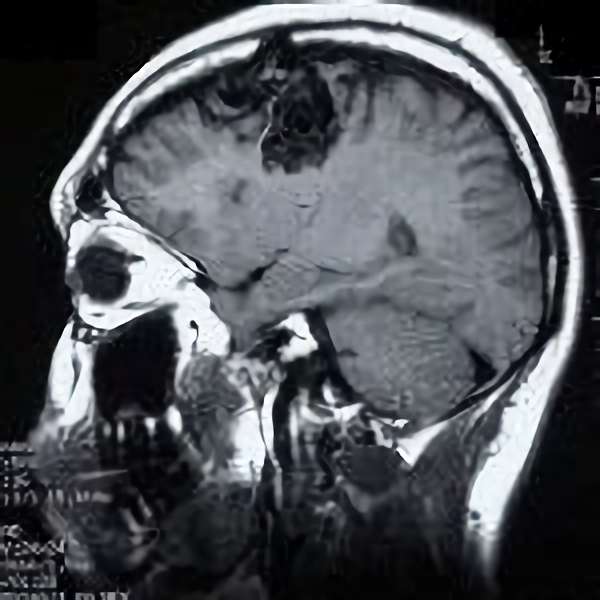

脳血管撮影

手術前

手術後